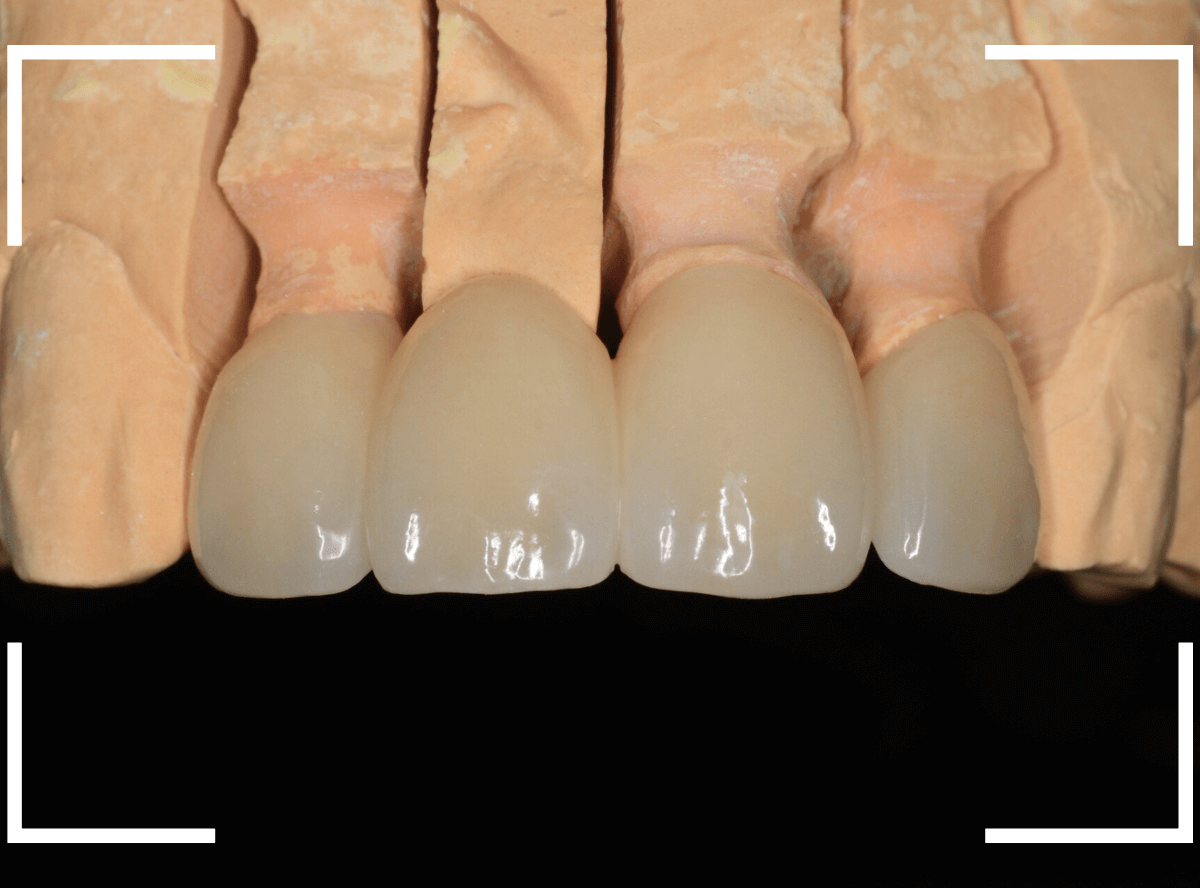

完成の前に、ジルコニアフレームにワックスを盛ったもので、患者さんと完成型のシュミレーションをします。

患者さんからも、ゴーサインをもらったのを確認して、完成させます。

微調整をして、最終setしたところです。

患者さんにも満足していただけたようで、ホッとしました。

セラミックの舌触りにも驚かれていました。